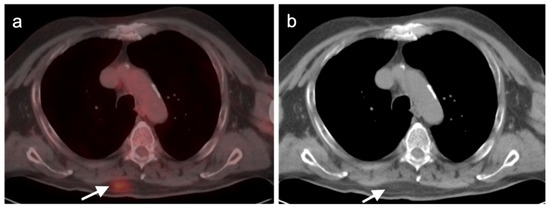

- Tatci, E.; Ozmen, O.; Gokcek, A.; Biner, I.U.; Ozaydin, E.; Kaya, S.; Arslan, N. 18F-FDG PET/CT rarely provides additional information other than primary tumor detection in patients with pulmonary carcinoid tumors. Ann. Thorac. Med. 2014, 9, 227–231. [Google Scholar] [CrossRef]

- Venkitaraman, B.; Karunanithi, S.; Kumar, A.; Khilnani, G.C.; Kumar, R. Role of 68Ga-DOTATOC PET/CT in initial evaluation of patients with suspected bronchopulmonary carcinoid. Eur. J. Pediatr. 2014, 41, 856–864. [Google Scholar] [CrossRef]

- Komek, H.; Can, C.; Urakçi, Z.; Kepenek, F. Comparison of (18F)FDG PET/CT and (68Ga)DOTATATE PET/CT imaging methods in terms of detection of histological subtype and related SUVmax values in patients with pulmonary carcinoid tumors. Nucl. Med. Commun. 2019, 40, 517–524. [Google Scholar] [CrossRef]